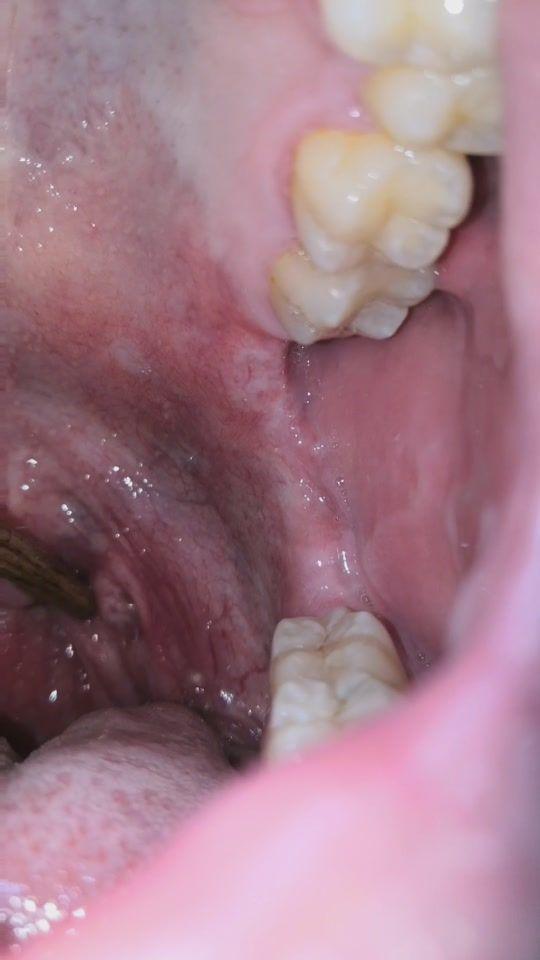

扁桃腺结石症状- 扁桃体结石的症状 症状类似慢性扁桃体炎。若结石周围有化脓感染,可有咽痛不适与反射性耳痛;重者感吞咽困难,言语含糊不清,口涎增多,张口受限等。 因为结石多陷入扁桃腺隐窝那就看看自己有木有这样的症状吧! 1、咽部不适感,干燥,发痒或轻度疼痛等; 2、每遇到感冒、受凉或烟酒刺激后咽痛就会发作,并有一种被什么东西堵塞了的感觉; 3、说话时还会有口臭,那是

出现扁桃体结石,并伴随明显症状后,应当就医进行相关检查。 一般小结石不需要手术治疗,医生会通过 刮匙、医疗用钳将结石去除; 而大结石则需要动一个小小的手术, 麻醉患者的扁桃第一,喉咙有没有经常分泌很臭的痰,咽下去觉得很恶心,如果有的话,说明是有 扁桃体结石 了。 第二,呼吸有没有感觉到臭味,你往外长呼一口气,如果鼻子能感觉出臭味,说明是有扁桃体结石了。 什么是扁桃腺结石 扁桃体结石主要是由于坏死细胞、粘液、唾液和食物等物质的残渣,硬化后所形成的。 扁桃体结石的个数,多少不一。 一般没有特殊症状,主要会使口腔发生难闻

出现扁桃体结石,并伴随明显症状后,应当就医进行相关检查。 一般小结石不需要手术治疗,医生会通过 刮匙、医疗用钳将结石去除; 而大结石则需要动一个小小的手术, 麻醉患者的扁桃方法3通过漱口去除和预防结石 1 进食后,用漱口水漱口。 结石通常由残留在扁桃体隐窝的食物残渣形成,所以在进食后漱口是很明智的做法。 漱口不只能改善牙齿和牙龈健康,还能让食物残渣脱落, 症状类似慢性扁桃体炎。 若结石周围有化脓感染,可有咽痛不适与反射性耳痛;重者感吞咽困难,言语含糊不清,口涎增多,张口受限等。 有感染时,常自觉口臭。 有时结石可自扁桃